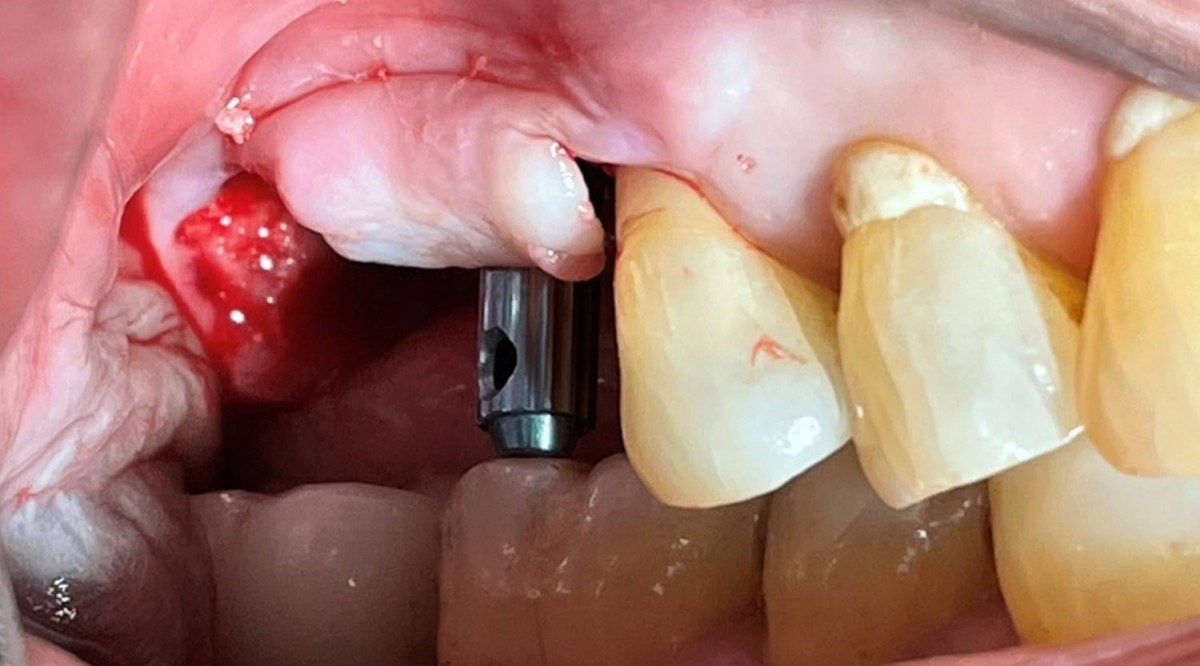

Maxillary Sinus Graft, 2 Implants, Crown Contouring

<GCaks> A 56-year-old male patient had pain-inducing caries, and perio-involved tooth mobility resulted in a tooth fracture at 1st molar. And it was removed months ago. He was a heavy smoker and showed poor oral hygiene.